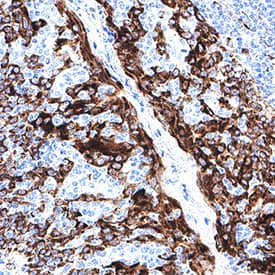

Detection of CKAP4/p63 in Human Colon.

CKAP4/p63 was detected in immersion fixed paraffin-embedded sections of human colon using Mouse Anti-Human CKAP4/p63 Monoclonal Antibody (Catalog # MAB11600) at 5 µg/ml for 1 hour at room temperature followed by incubation with the Anti-Mouse IgG VisUCyte™ HRP Polymer Antibody (Catalog # VC001). Before incubation with the primary antibody, tissue was subjected to heat-induced epitope retrieval using VisUCyte Antigen Retrieval Reagent-Basic (Catalog # VCTS021). Tissue was stained using DAB (brown) and counterstained with hematoxylin (blue). Specific staining was localized to the cell surface and cytoplasm. View our protocol for IHC Staining with VisUCyte HRP Polymer Detection Reagents.